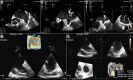

Figures